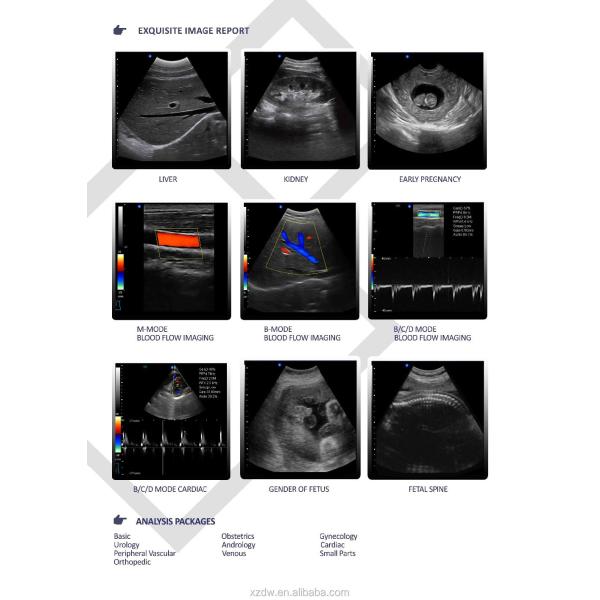

Imaging mode : B+B,B+M,M

Display mode : B,B+B,M,B+M

Main features for ultrasound pregnant 4d :

With high precision digital beam forming and Doppler ultrasonic imaging technology, Pro incorporated

the latest image processing technologies such as THI, speckle reduction, multi-beam parallel processing

and efficient full-digital image management system is easy to acquire better image. Special measurement

software packages, flexible configuration and ergonomical design greatly increase operators clinical

diagnosis accruacy and analysis efficiency.

Technical Specification for vascular ultrasound scanners:

-Application

Abdomen, OB&GYN, cardiology, vascular and small parts, urology, musculoskeletal, pediatrics and etc

-Displaying mode

B, 2B, 4B, left&right, B|M, B|D, PW, M, B mode, part zoom, B|C|D, B|C|M, B|C,

duplex, PW, CFM, CPA

-Image processing

THI, speckle-reduction, color coder, frame averaging, micro- angle adjustment, wall filter, 256

grey scale, scanning angle/width control, composit processing of tissue and blood flow image

-Measurement & report packages

GYN(four edition for GA calculation), cardiac, vascular, urology, andriatrics, peripheral vascular, multiple births, orthopedic surgery and etc.

GH-L5 Portable Ultrasound Machine 4d Diagnostic Ultrasound Pregnancy Machine Images |